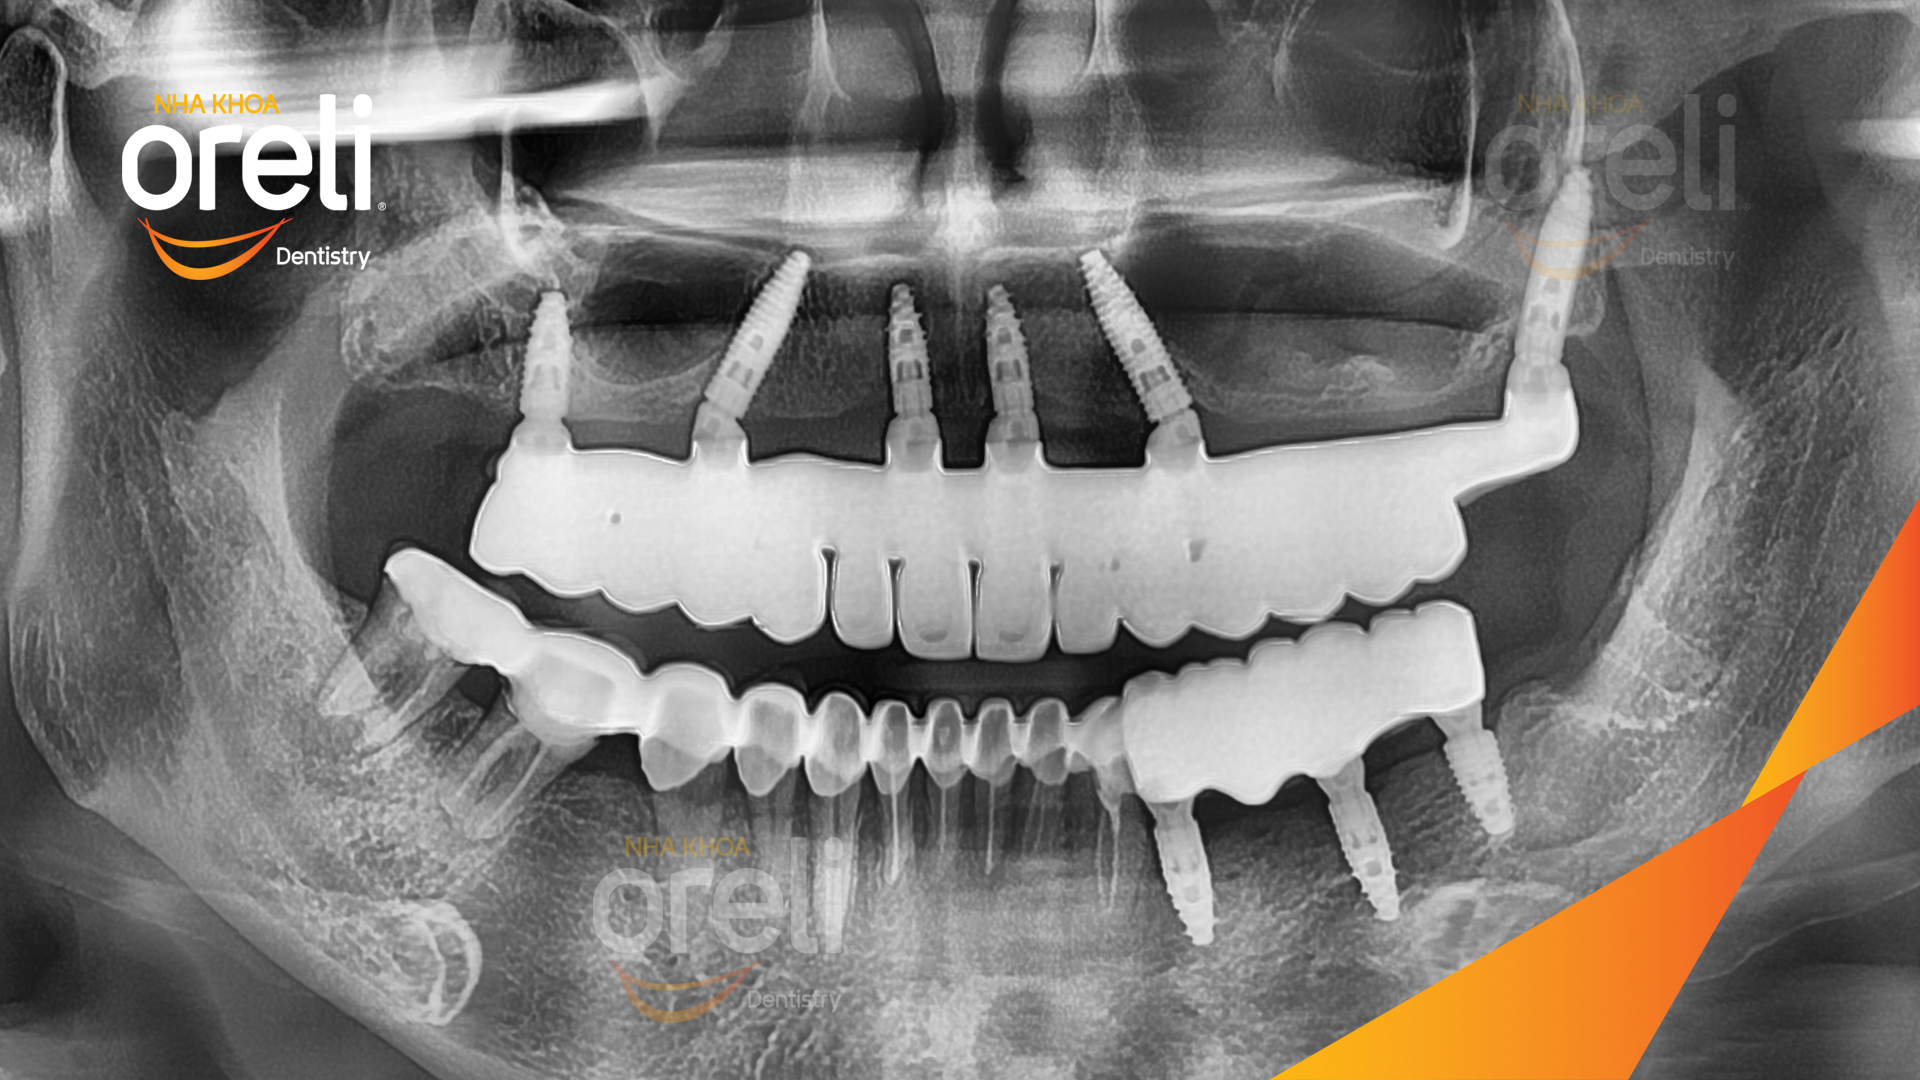

Ca trồng răng implant hàm trên và ba răng hàm dưới hình ảnh trước sau

Ca trồng răng implant toàn hàm phục hồi ăn nhai và thẩm mỹ nụ cười. Kết quả thực tế trước và sau điều trị tại Nha khoa Oreli.

Tình trạng: Cầu răng sứ hàm trên lung lay, các chân răng cũ tiêu xương

Giải pháp: Cắt bỏ cầu răng nhổ các chân răng trồng implant all on six

Kết quả: Thẩm mỹ tự nhiên ăn nhai chắc chắn

Hình ảnh thực tế